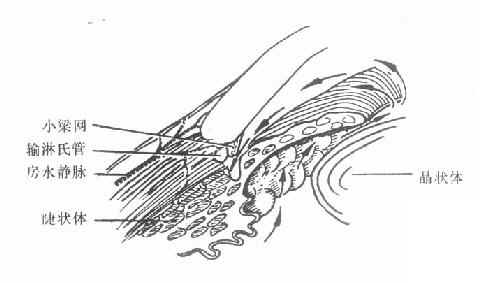

4.缓解期:急性发作的病例,大多数经过治疗,或者极少数未经治疗,症状消失,关闭的房角重新开放,眼压降至正常,病情可以得到暂时缓解,局部充血消失,角膜恢复透明,视力部分或完全恢复。个别短期无光感的病列,若及时降低眼压,尚可恢复一些有用视力。但这些情况只是暂时的,如不及时进行手术治疗,随时仍有急性发作的可能。此期称为急性闭角型青光眼缓解期,若及时施行周边虹膜节 除术,可防止急性发作。(图10-1,10-2)。

图10-1 闭角青光眼临床前期

(房角窄、房水流动正常、无粘连)

(箭头显示房水流动)